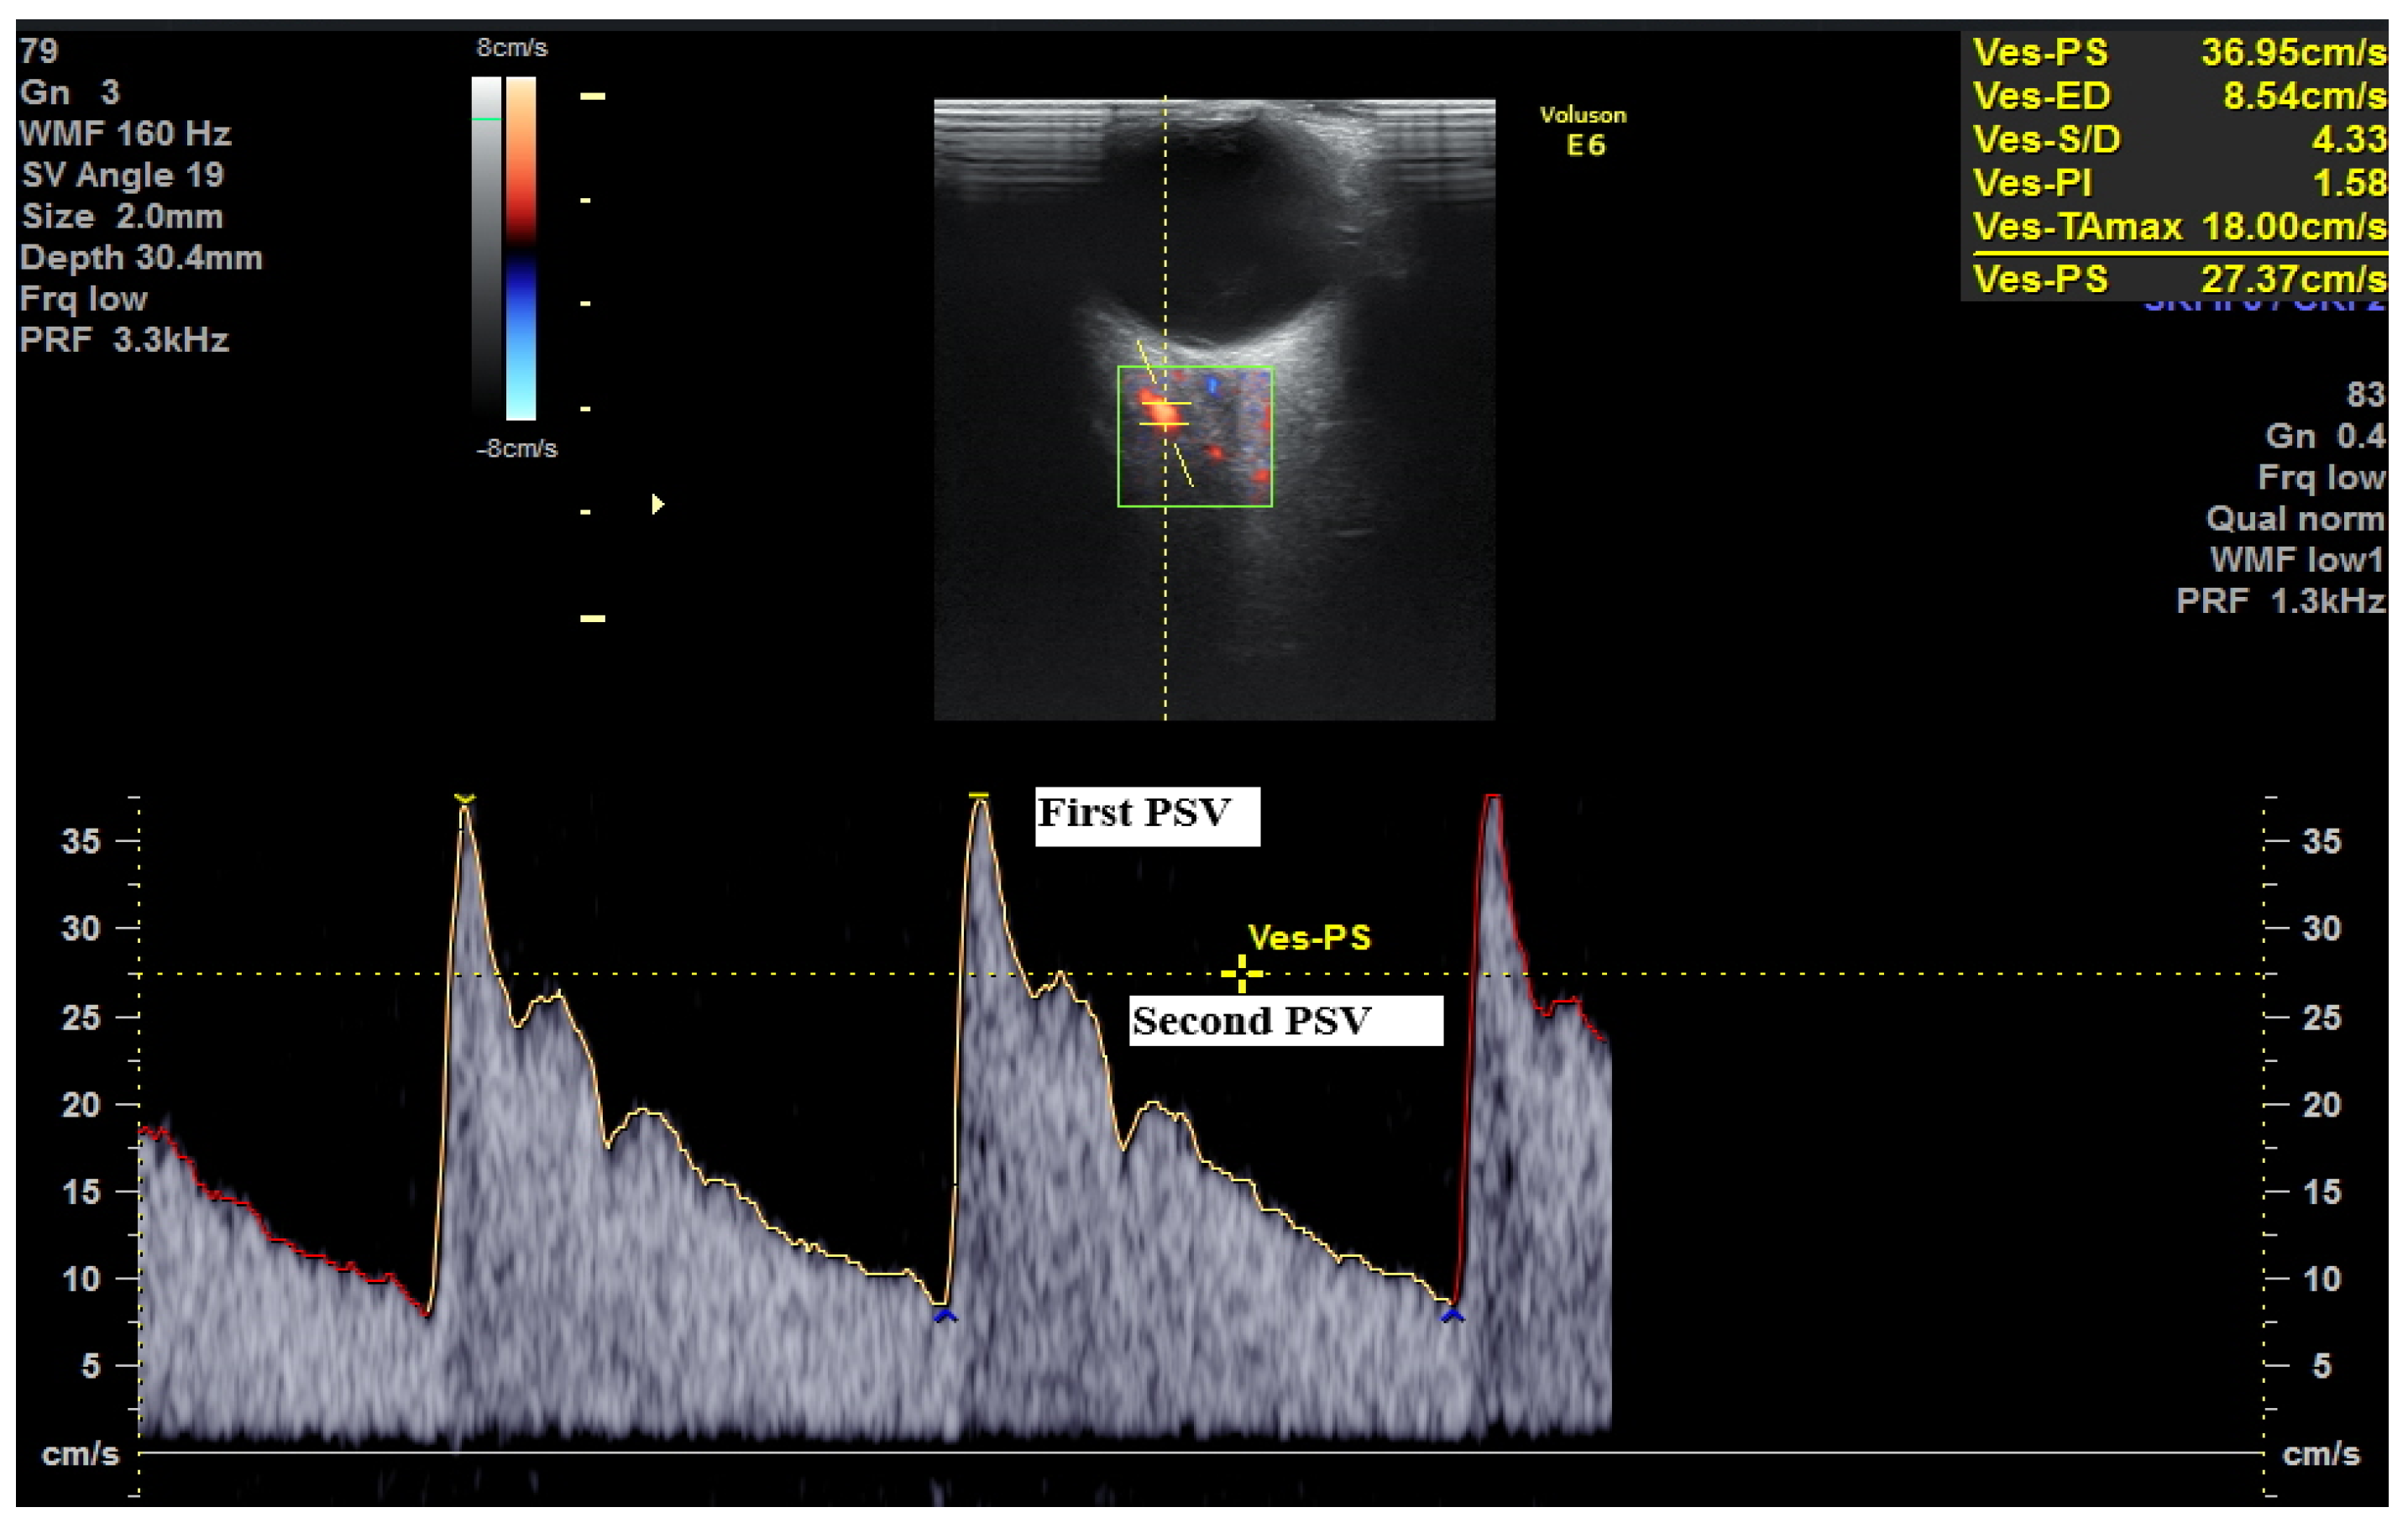

| PSV Ratio (P2/P1) | Low (P2 is significantly lower than P1; ratio typically < 0.6) | Elevated (P2 approaches or exceeds P1; ratio often > 0.65–0.75, depending on gestational age) | The elevation of the second peak (P2) signifies a loss of normal vascular tone and autoregulation, leading to a “high-flow” state. |

| Second Peak Systolic Velocity (PSV2 or P2) | Lower absolute velocity | Elevated (A cut-off of ≥43.75 cm/s has been identified as highly discriminatory) | A direct measure of increased systolic flow velocity, correlating with increased cerebral perfusion pressure. |